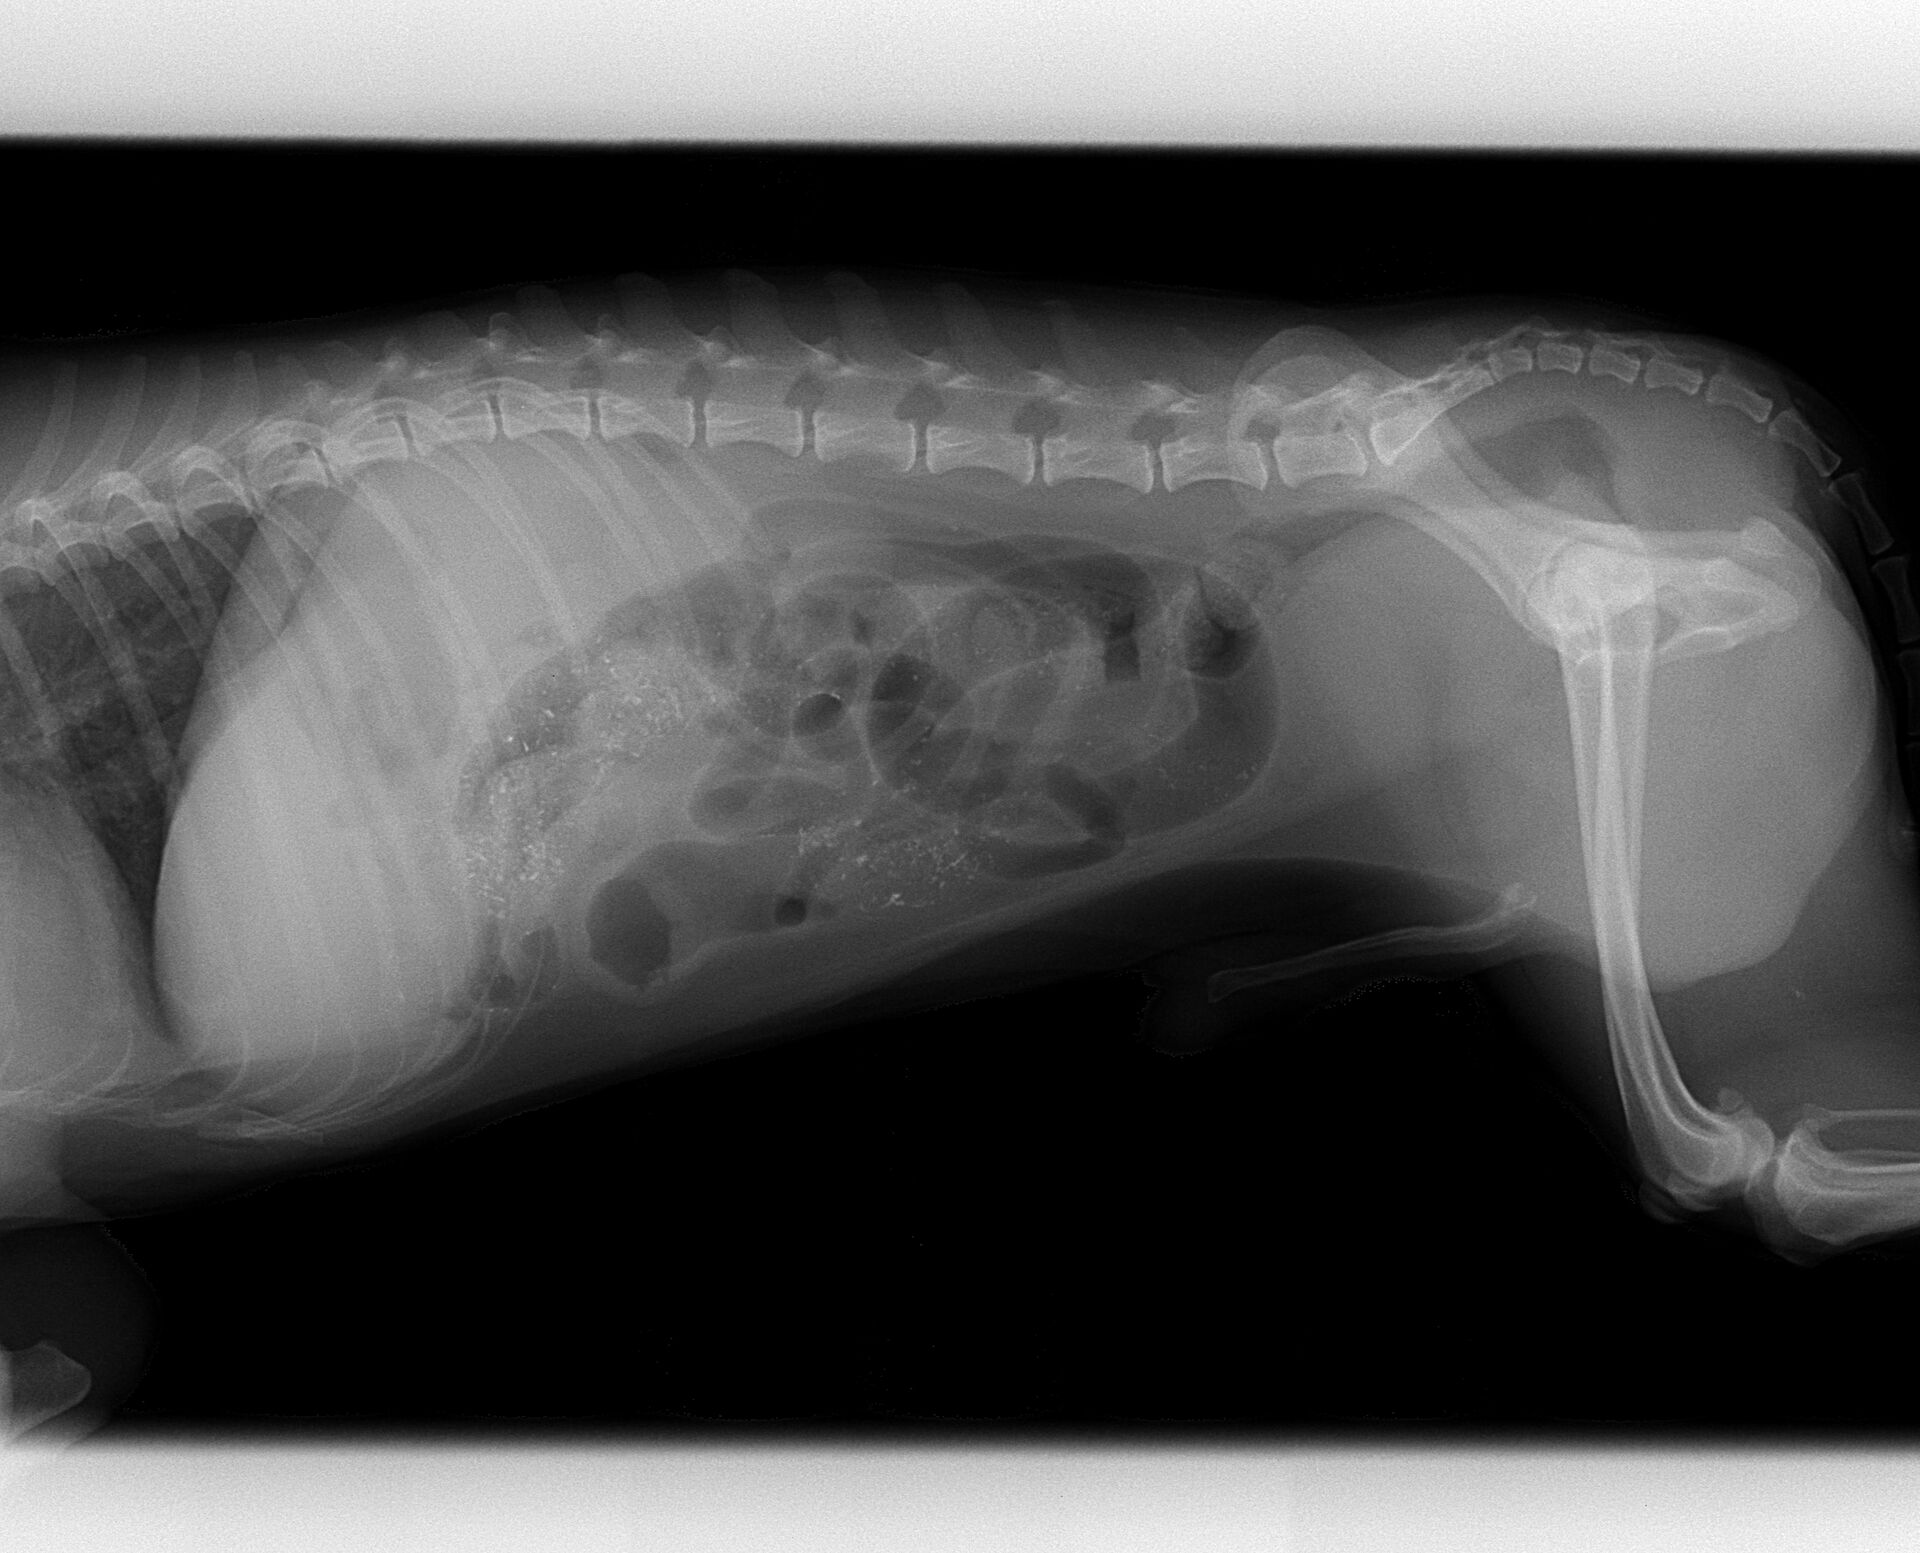

10歳、オスのトイプードルが1か月くらい前からよく吐くようになり、ここ3日くらいは全く食べなくなったということで来院されました。かなり痩せていて、脱水も起こしていました。腹部を触診すると中央部に500円玉くらいの硬いものが触れました。異物の誤嚥が考えられたので、レントゲンを撮りました。その写真が下です。

小腸内にかなりのガスが充満しているのがわかります。腹部に硬いものが触診でき、腸内にガスが充満していることから、異物による腸閉塞が強く疑われました。症状が現れてから時間が経過し、痩せて状態が良くないので、急いで手術する必要があるのですが、このままの状態で手術すると体力的に厳しい可能性があります。そこで、その日は少しでも状態をよくするために点滴をし、翌日に手術をすることにしました。